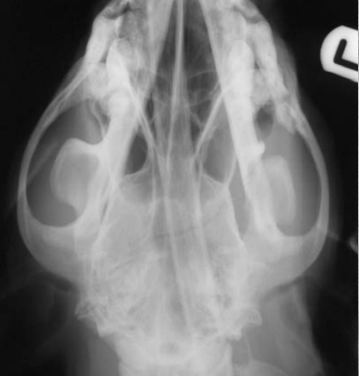

identify pathology

3 neoplasia examples (but inflammation looks very similar) observe difference in density between sides of jaw. it shouldn't be too dense nor too dark (lytic changes). You should be able to see turbinate structures in normal states. But note, that fluid will also obscure structures.